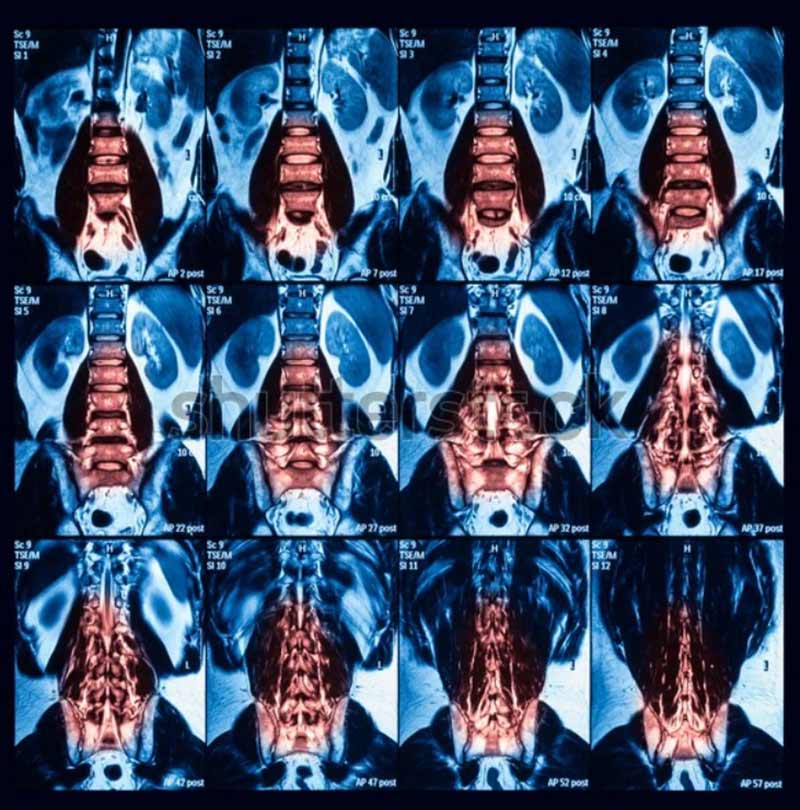

Nếu triệu chứng chưa rõ ràng, bác sĩ có thể yêu cầu bạn thực hiện các nghiên cứu hình ảnh như X-quang, CT hoặc MRI để hỗ trợ trong quá trình chẩn đoán và kiểm tra các vấn đề khác liên quan đến cột sống và hông.

Để xác nhận nguyên nhân gây đau, bác sĩ có thể thực hiện tiêm chẩn đoán vào khớp cùng chậu. Khớp cùng chậu sẽ được tiêm chất gây tê cục bộ và thuốc corticosteroid. Quá trình tiêm sẽ được thực hiện dưới sự hướng dẫn của hình ảnh X-quang để đảm bảo kim được đặt chính xác trong khớp cùng chậu.

Xem chi tiết: Hình ảnh viêm khớp cùng chậu

Mức độ đau của bạn sẽ được đánh giá trước đó, sau tiêm từ 20 – 30 phút và được theo dõi trong tuần tiếp theo. Nếu mức độ đau của bạn giảm hơn 75%, thì sự liên quan đến khớp cùng chậu sẽ được xác nhận. Nhưng nếu mức độ đau không thay đổi sau tiêm, có thể khớp cùng chậu không phải là nguyên nhân gây chứng đau thắt lưng.